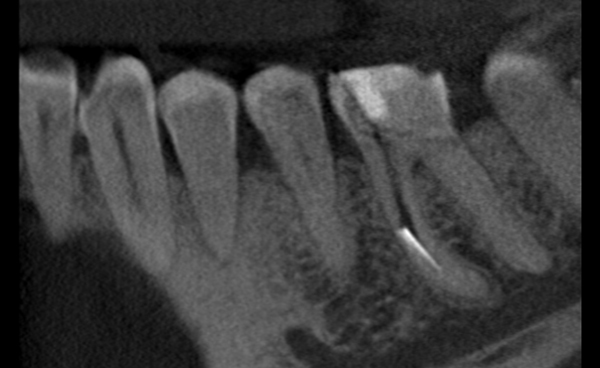

27-latni pacjent zgłosił się do naszej placówki z prośbą o pomoc polegającą na kontynuacji leczenia kanałowego, trwającego już wiele miesięcy. Leczenie przedłużało się z powodu powikłania w postaci złamanego narzędzia endodontycznego, które uniemożliwiało dezynfekcję systemu kanałowego na całej długości. Dodatkową trudnością była lokalizacja narzędzia w połowie długości korzenia za krzywizną kanału, co uniemożliwiało jego widoczność w mikroskopie. Podjęto próbę ominięcia („by passa”) narzędzia, co niestety nie powiodło się. Nieocenioną pomocą w tym precyzyjnym zabiegu okazała się tomografia wolumetryczna, która „sięgała, gdzie wzrok nie sięgał” i ułatwiła bezpieczne usunięcie narzędzia, a następnie pełną dezynfekcję i szczelne wypełnienie systemu korzeniowego. Zabieg trwał 4 godziny (2 wizyty po 2 godziny) i dzięki olbrzymiej cierpliwości pacjenta i precyzji operatora zakończył się sukcesem.